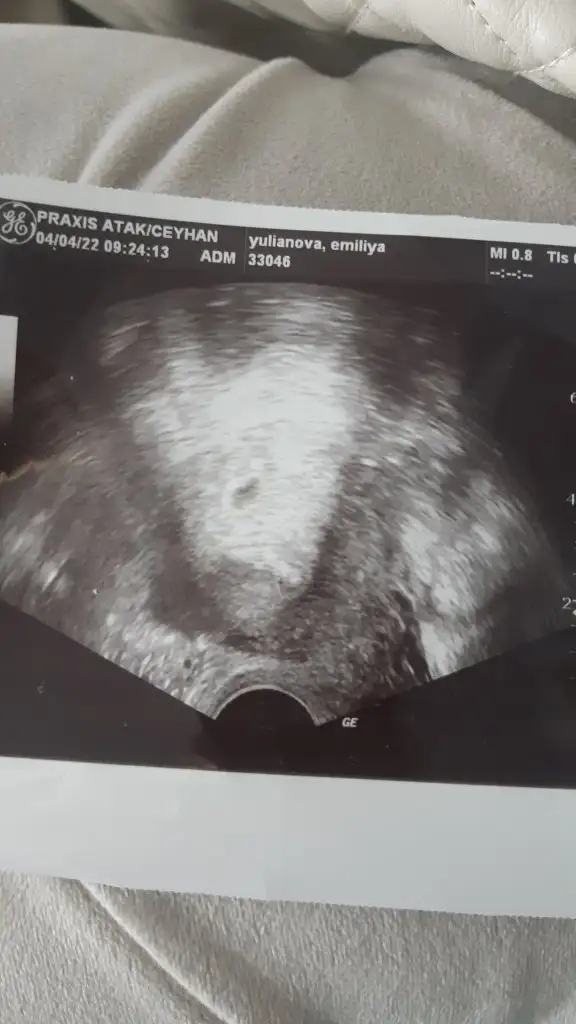

Merhaba 5 hafta 2 günlük bebegim banada tahmin yaparmisinis şimdiden çok teşekürler.

Eklentiler